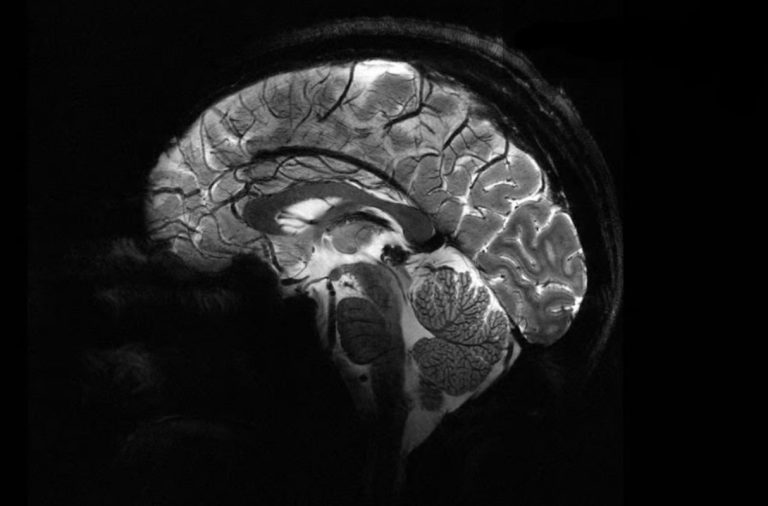

قدرتمندترین دستگاه MRI جهان اولین اسکن مغزی خیرهکننده را ثبت کرد. به گزارش رسانه مدیاتی، قدرتمندترین دستگاه MRI جهان با